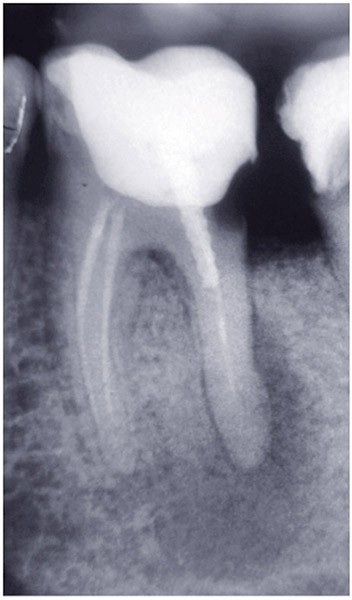

Dans un environnement parodontal sain, la chronologie des traitements conservateurs suite à la pathologie carieuse serait la suivante : le traitement endodontique de première intention, le retraitement endodontique et la chirurgie endodontique, voire l’amputation radiculaire. En cas d’échec, l’alternative implantaire pourra être envisagée (fig. 1).